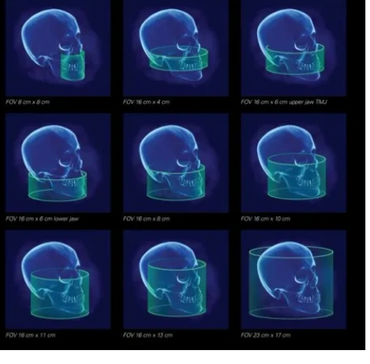

FOV Field of View Are options that allows us to choose the best x-ray beam size/ratio for a study.

We can isolate an area from 8cm x 8cm to as large as 23cm x 17cm. We can customize the field as well.

Voxel: We also can choose the voxel size of the scan. Voxel derives from the terms combine from Pixel and Volume. The best depiction that I can give you is a rubics cube.

The smaller the cube the higher definition of the scan. Our average scan we take is at a .25mm voxel. This allows us to make cross-sectional slicings down to .25 mm, and we typically will measure and print at 1mm. (depending on the study ordered).